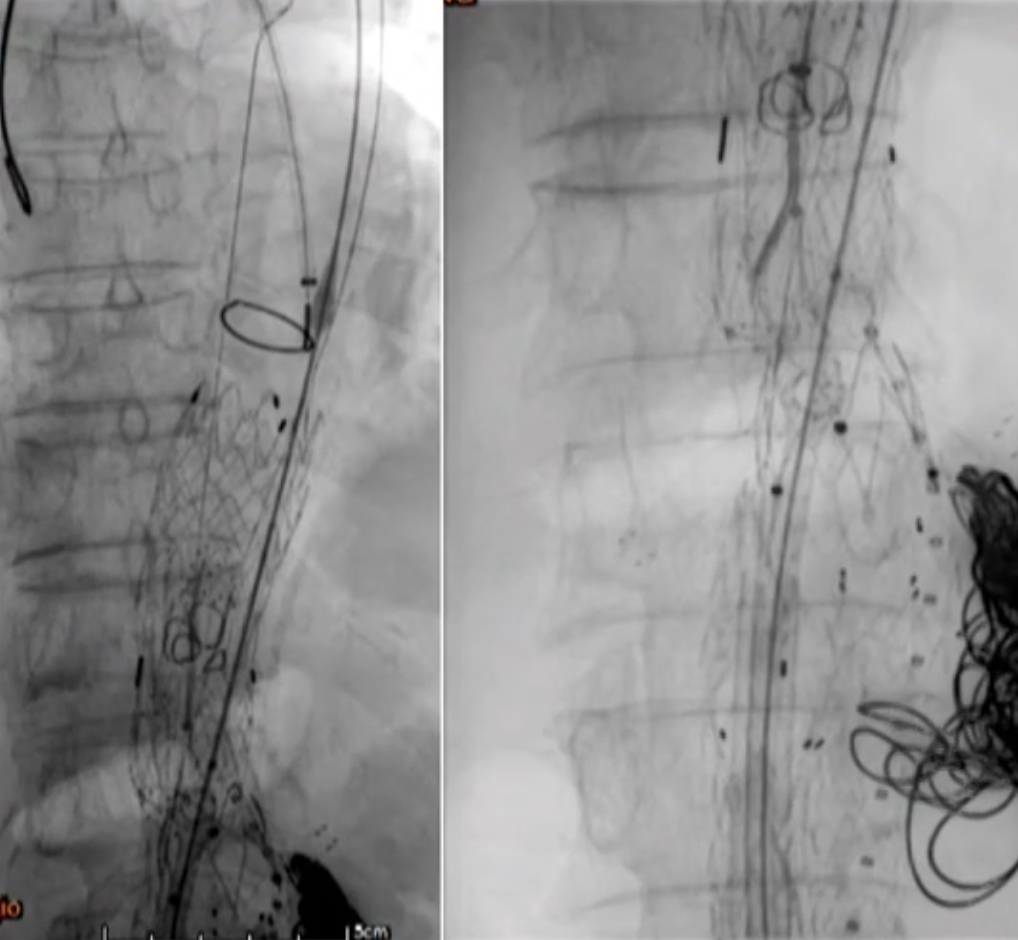

77岁男性,腹主动脉瘤EVAR后2年,再发腹痛入院。

既往:腹主动脉瘤,外院4次腔内手术史

2022年8月12日:EVAR+双肾动脉烟囱支架重建

2022年8月24日:右髂支闭塞,左髂支狭窄,右侧行Angiojet PMT,右髂支远端植入裸支架,左侧髂支中段植入裸支架,右侧保留导管CDT

2022年8月25日:右髂支血栓残余,再次PMT,右髂支中段植入裸支架

2023年3月24日:CT随访发现Ia型内漏,瘤腔弹簧圈栓塞+生物蛋白胶注射

诊断:术后CT复查Ia型内漏持续,动脉瘤2个月增大7mm

手术难点:

入路扭曲狭窄,双侧髂支多枚补救性裸支架

双肾动脉烟囱支架受裸架压迫紧贴主动脉后壁,左肾动脉烟囱支架打横

裸架丝遮挡SMA开口

弓部动脉瘤

治疗方案:PMEG拓展近端锚定区,重建CA、SMA、RRA和LRA

精准PMEG:窗口/分支无法打开,且径线缠绕,肾动脉烟囱支架挤压,弓形不适合进大鞘

容错PMEG:容错空间相对较大,对弓形和上肢入路要求低

35-14-140mm分叉型支架,缝制内分支并固定,RRA、LRA:5mm Viabahn,CA、SMA:7mm Viabahn

分支预置导丝,回装支架

超选SMA,桥接8-100mm Viabahn,内衬8-60mm Absolute裸支架

超选CA,桥接8-100mm Viabahn

超选RRA烟囱支架,桥接6-100mm+6-50mm Viabahn

超选LRA烟囱支架,桥接6-100mm Viabahn

右侧:16-16-140mm Excluder髂腿;

左侧:16-16-120mm Excluder髂腿

术后造影